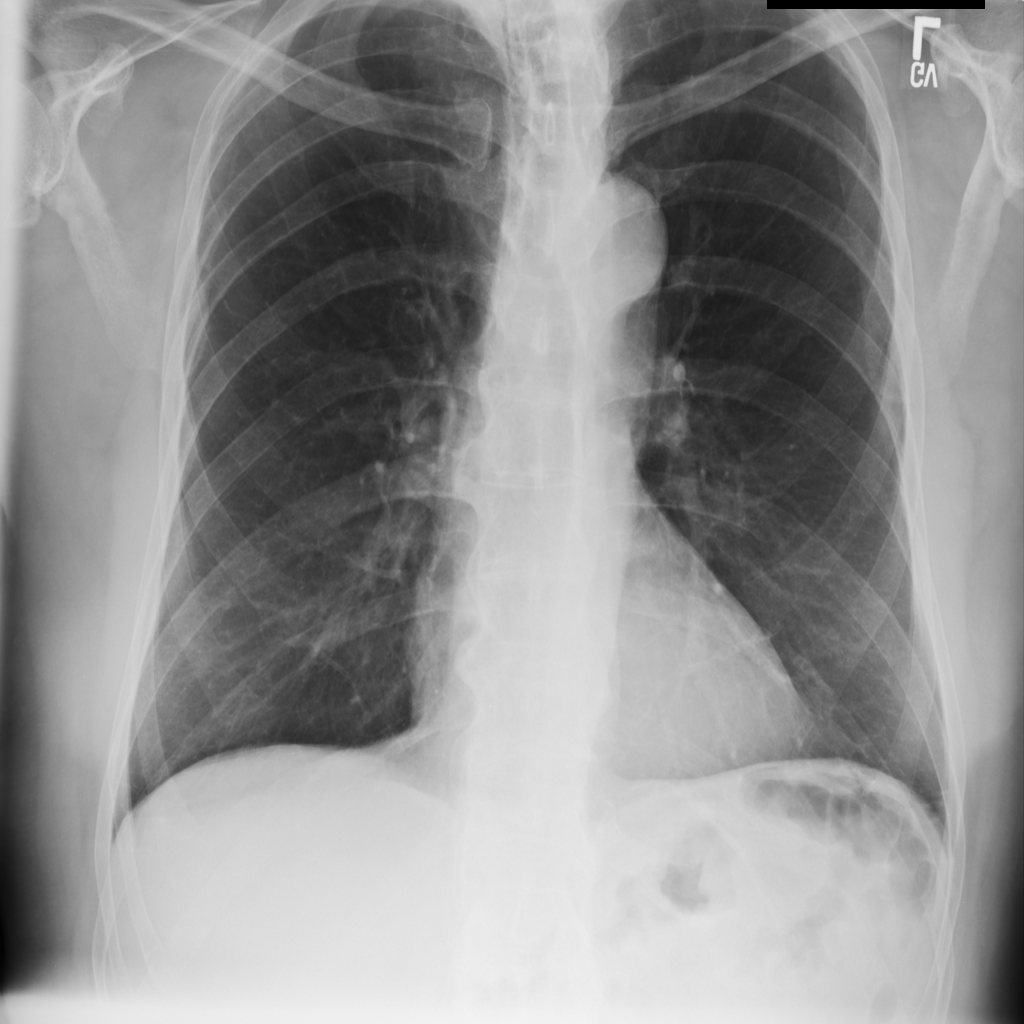

PAT-C8B7 · IMG-000Emphysema

PAT-C8B7 · IMG-000

PA